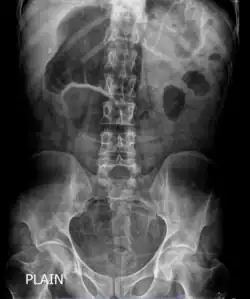

| X-ray showing distended stomach and bowel loops. Dilated bowel loops are a characteristic of chronic intestinal pseudo-obstruction. | |

The diagnosis of CIPO is mostly clinical, backed by radiographic documentation of dilated bowel with air-fluid level after exclusion of organic lesions obstructing the gut lumen, as determined by radiologic and/or endoscopic examinations. Thus, diagnostic investigations in patients with suspected CIPO are required to rule out mechanical blockage, identify possible sources of secondary forms, investigate underlying pathophysiological mechanisms, and reveal potential consequences.[24]

In order to look into possible intestinal obstruction, radiologic examinations are essential. Simple and cheap to perform, plain film x-rays can show the traditional indicator of air-fluid levels and dilated bowel loops, which is best seen in the erect film.[25] Abdominal x-rays, however, are unable to definitively differentiate between genuine mechanical intestinal obstruction and pseudo-obstruction.[26] Afterwards, additional information is obtained by abdominal computed tomography (CT) imaging in order to rule out an extraluminal, gut wall, or intraluminal mechanically obstructive lesion.[25]